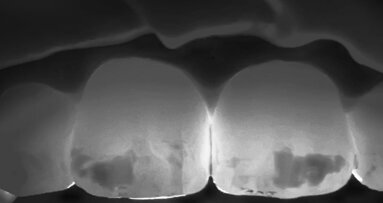

Il venerdì inizia con “The Quality of Esthetics – 7 impulse lectures”, con partecipanti a numero chiuso e relatori quali Markus Lenhard, James Russel, George Eliades, Nelson Silva, Sameer Puri, moderati da Diane Rekow, Direttrice del King’s College London Dental Institute, che ha patrocinato l’evento. La Direttrice viene introdotta da Robert Ganley, con queste parole: «Sono onorato di averla qui. Professoressa e ricercatrice, autrice di innumerevoli pubblicazioni, ha dimostrato che il Disilicato di Litio è il migliore dei materiali. Diane Rekow è sempre stata un’avanguardia, anche nel digitale e nel Cad». Replica la Rekow: «Voglio ringraziare questa azienda che ha dato un grande contribuito in questa materia e alla carriera di tanti di noi». Frase per nulla scontata, che precede la sua relazione tecnica introduttiva al circolo pomeridiano, eccezionale secondo il giudizio di tanti nei corridoi del coffe break. In questa sessione si è parlato di nuovi materiali rispondendo a due principali interrogativi: quale e quando il successo, quanto la longevità.